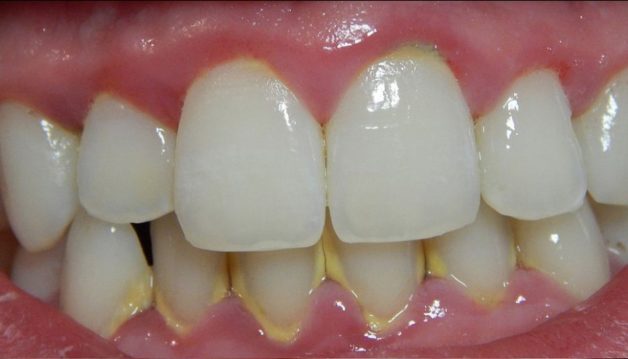

Hình ảnh cao răng bám đầy răng bệnh nhân

- Hạn chế nguy cơ mắc các bệnh lý răng miệng: cao răng là nơi trú ngụ của rất nhiều vi khuẩn có hại – chúng chính là nguyên nhân hàng đầu gây ra các bệnh lý như sâu răng, tụt lợi, viêm nha chu, mòn men răng,…

- Răng trắng sáng hơn: một trong những nguyên nhân khiến răng bị xỉn màu chính là các mảng bám cao răng. Việc loại bỏ cao răng sẽ mang lại một hàm răng sáng bóng và tăng tính thẩm mỹ cho cả khuôn mặt.